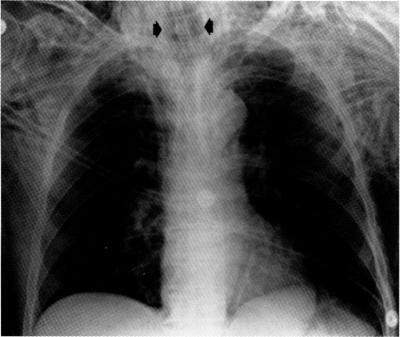

Lethal tracheal dissolution during treatment for thyroid lymphoma.

• A case of primary thyroid T cell lymphoma leading to lethal tracheal perforation during chemotherapy is described.